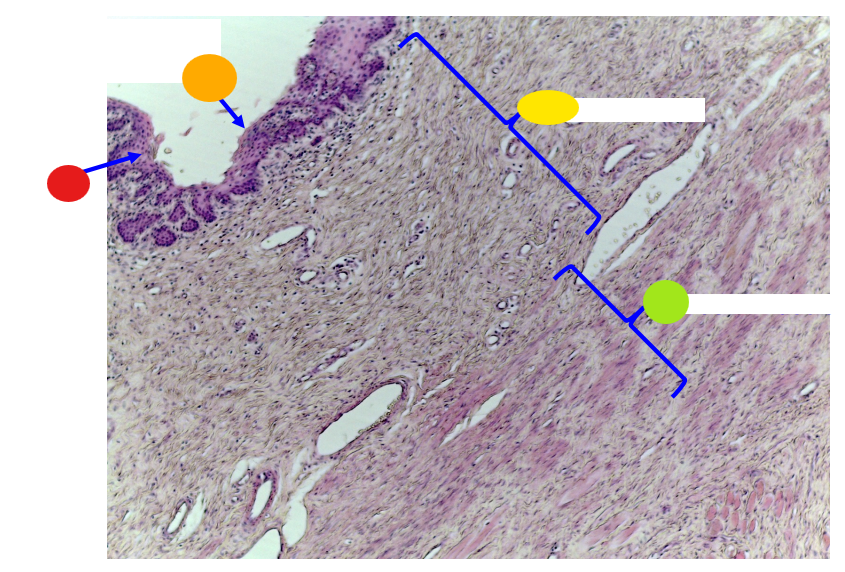

red

serosa

orange

lumen

yellow

mucosa

light green, name and tissue type

muscularis, smooth muscle

dark green

serosa

What is this?

uterine tube

red

lamina prioria

orange

simple columnar epithelium

yellow

lumen

what is this?

uterine tube

What tissue type is the epithelium/inner linning of the uterine tube?

simple columnar epithelium